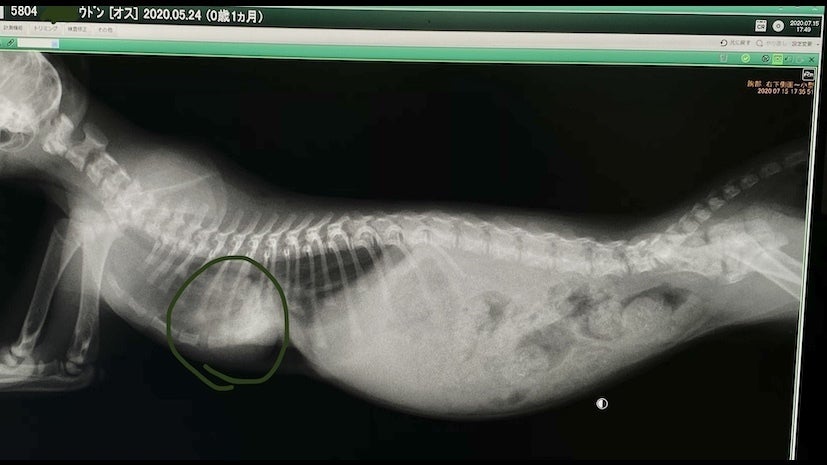

レントゲンを見た感じだと肋骨が内蔵(心臓)にくい込んでいる(通常じゃ有り得ないことなのでまだ未確定)可能性があり手術の難度も上がり、費用も通常よりもかなり高額になるとの事です。

見にくいですが肋骨の下に心臓(緑の丸の部分)があります。